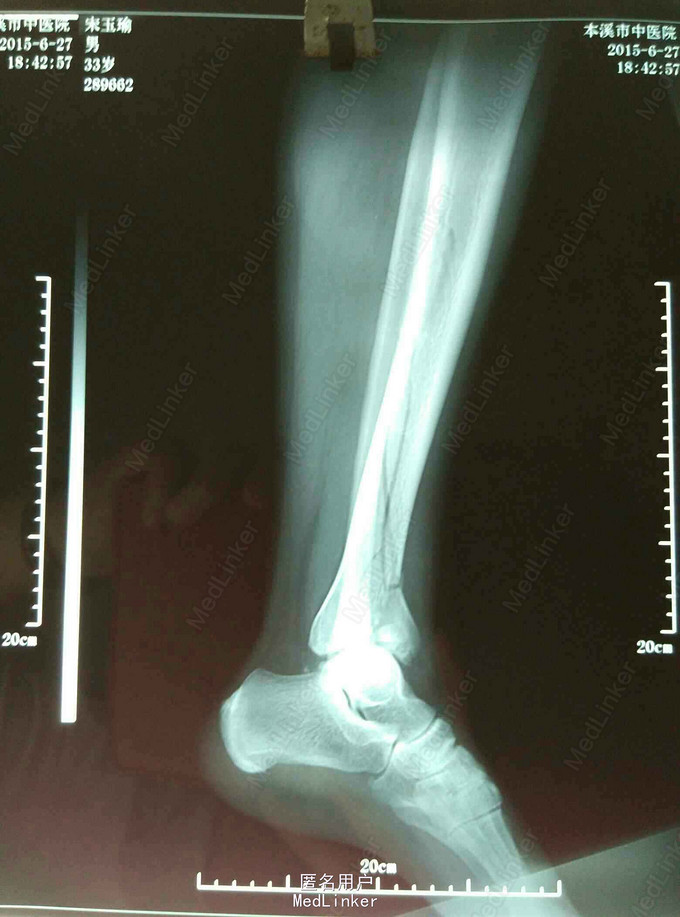

患者女33岁左踝刺痛活动受限5小时 ,患者5小时前擦玻璃时不慎从10米高处坠落伤后来诊。既往:健康。否认肝炎结核等传染病史。

查:左踝肿胀严重,压痛(阳性),左小腿中段压痛。左下肢功能障碍。 足背动脉搏动清,足趾活动良好。 DR:左胫骨pilon骨折。

左胫骨pilon骨折

外固定支架固定。